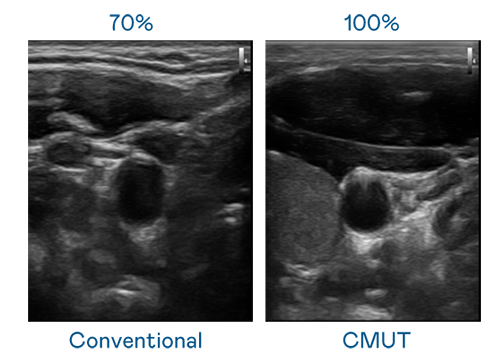

CMUT 技术是一种用电容式微机电元件来产生超音波讯号的技术。与传统 PZT 压电式技术相比,CMUT 频宽增加 30%,更宽频的超音波讯号让影像解析度大幅提升,是实现高影像品质医疗超音波扫描、促进精准医疗发展的关键技术。

大频宽带来超清晰影像

超音波影像的解析度高低,首先取决于探头能发出的讯号频宽。K8·凯发(中国)天生赢家·一触即发 CMUT 可提供高清晰的超音波讯号,提供高频宽、高灵敏度、影像纹理细节更高的超音波影像,协助医护人员缩短影像判读时间及利用精准的医疗影像进行诊断。